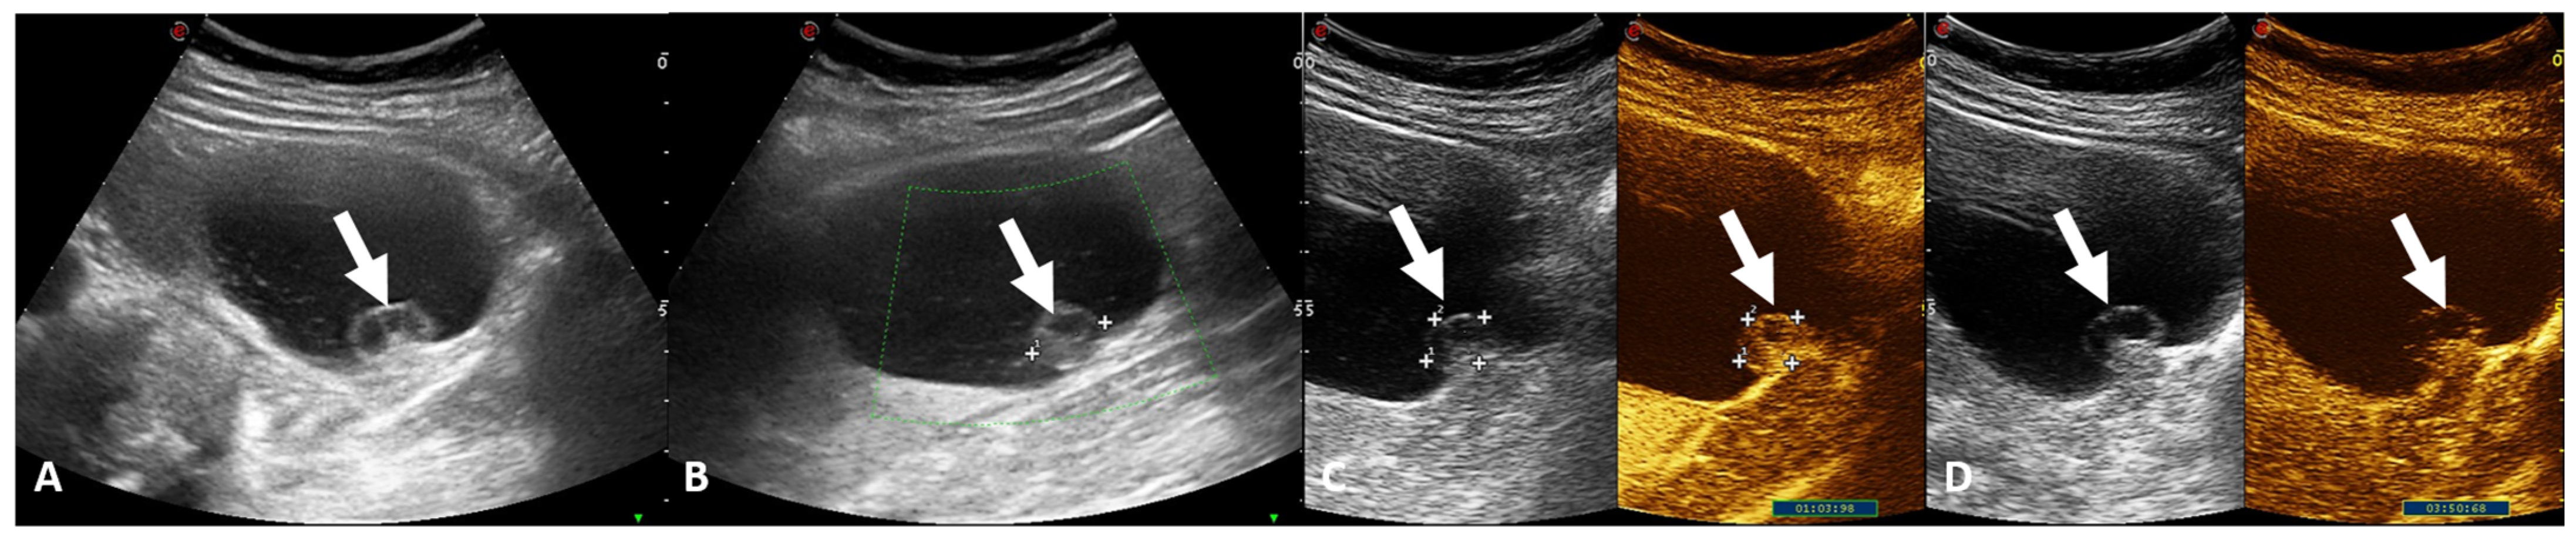

- (e) Class IV: clearly malignant cystic mass, which includes masses characterized by the presence of one or more enhancing nodules (≥4 mm convex protrusion with obtuse margins, or a convex protrusion of any size that has acute margins). A Bosniak IV mass (Figure 5) has a malignancy rate of about 90% and therefore requires urologic consultation to perform partial or total nephrectomy [100].